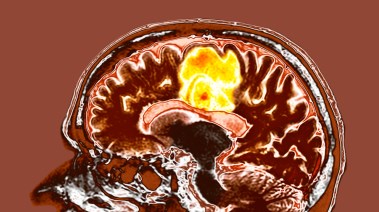

تحدثت دراسة حديثة أجراها معهد الطب النفسي وعلم النفس والأعصاب في كينجز كوليدج لندن عن دور التحفيز الكهربائي للدماغ في علاج شراهة الأكل والسمنة، بحسب صحيفة ديلي ميل البريطانية.

وبحسب الدراسة فإن تقنية التحفيز بالكهرباء والتي تسمى (tDCS)، تعني التحفيز بالشكل المباشر عبر الجمجمة، وهو أسلوب غير جراحي يتضمن استخدم تيار كهربائي آمن ومنخفض على مناطق محددة من فروة الرأس، فوق القشرة الحركية أو قشرة الفص الجبهي.

وتقوم تلك التقنية على استخدام قطبين كهربائيين أو أكثر يوضعان على سطح فروة الرأس، مما يؤدي لتوصيل التيار ومن ثَم يتدفق عبر أنسجة المخ الـtDCS.

واستنتجت الدراسة أن الأشخاص الذين أُجريت عليهم تجربة التحفيز الدماغي بالكهرباء، انخفضت لديهم الشهية ونوبات الشراهة، من متوسط 20 مرة شهريًا إلى حوالي ست مرات فقط، وكل ذلك في مدة قدرها ستة أسابيع.

كما لاحظت الدراسة انخفاضًا ملحوظًا في الوزن قدر بنحو 4 كيلوجرامات نتيجة للتحفيز الكهربائي للدماغ، مما يعني قدرة تلك التقنية على التخلص من الوزن الزائد.

ووفق تصريحات للباحثة والمشاركة والمؤلفة الأولى للدراسة الدكتورة ميكايلا فلين قالت إن دراسة التحفيز الكهربائي للدماغ وعلاقتها بخفض الشهية والشراهة هي الأولى من نوعها، حيث تقدم علاجًا منزليًا يقدم نهجًا مختلفًا لعلاج اضطراب الشهية.

وأوضحت أن العلاجات الحالية لاضطراب الشهية عند تناول الطعام تكون فعالة فقط مع بعض الأشخاص فيما يحتاج باقي الأشخاص إلى مزيد من العلاج.